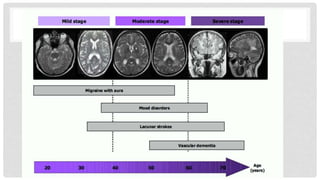

CADASIL

Arteriopatía cerebral con infartos subcorticales y leucoencefalopatía

Mutación heterocigota en el gen NOTCH3 cromosoma 19p13

AD

Aparición en la tercera década

43% infartos cerebrales tempranos

Penetrancia completa

Trastorno progresivo de los pequeños vasos arteriales del cerebro

Migraña, accidentes cerebrovasculares y lesiones de la sustancia blanca, con deterioro cognitivo.

CADASIL HALLAZGOS Y RM

• Entre los 20 y 30 años – lesiones hiperintensas en T2 en frontales y lóbulos temporales

de manera anterior

• 30-40 años – áreas hiperintensas periventriculares, cápsula externa, ganglios basales,

talamo y tallo cerebral

• > 40 años – infartos lacunares, lesiones hemorrágicas en el interior de la capsula

• > 50 años – infartos lacunares, sangrados microscópicos. Se encuentra vasculopatía

de arterias pequeñas que penetran en la sustancia blanca, las de mediano calibre

muestran estrechamiento, obliteración

• Las arterias afectadas muestran material granular denso cerca de las membranas